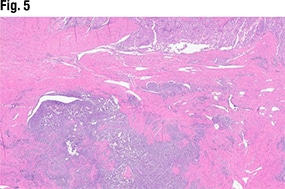

In Fig. 5 is another view of the myometrial invasion, with the myometrium shown in pink. In the purple portion of the image, “you can see these large nests of this more poorly differentiated part of the tumor infiltrating into the myometrium. So deeply invasive, solid, and some with glandular morphology,” she said.